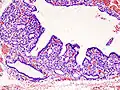

Hyperthyroidism is one of the most common endocrine conditions affecting older domesticated housecats. In the United States, up to 10% of cats over ten years old have hyperthyroidism.[59] The disease has become significantly more common since the first reports of feline hyperthyroidism in the 1970s. The most common cause of hyperthyroidism in cats is the presence of benign tumors called adenomas. 98% of cases are caused by the presence of an adenoma,[60] but the reason these cats develop such tumors continues to be studied.

The most common presenting symptoms are: rapid weight loss, tachycardia (rapid heart rate), vomiting, diarrhea, increased consumption of fluids (polydipsia), increased appetite (polyphagia), and increased urine production (polyuria). Other symptoms include hyperactivity, possible aggression, an unkempt appearance, and large, thick claws. Heart murmurs and a gallop rhythm can develop due to secondary hypertrophic cardiomyopathy. About 70% of affected cats also have enlarged thyroid glands (goiter). 10% of cats exhibit "apathetic hyperthyroidism", which is characterized by anorexia and lethargy.[61]